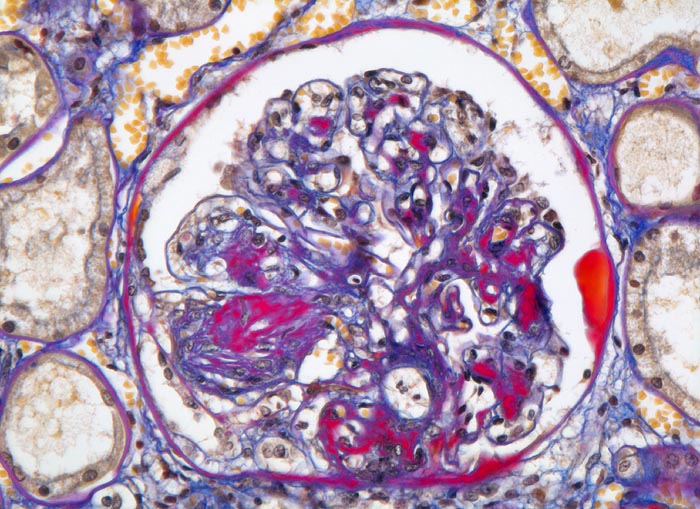

PathoPic – image database / PathoPic ID 4635 - Diabetische noduläre Glomerulosklerose Kimmelstiel-Wilson

Diabetische noduläre Glomerulosklerose Kimmelstiel-Wilson

Frühstadium der knotigen Ablagerung mit Hyperzellularität innerhalb des Knotens. Zusätzlich fokale mesangiale Matrixvermehrung. Das parietale Epithel der Bowman'schen Kapsel ist teilweise schaumzellig umgewandelt. Proteinablagerung in Form eines Kapseltropfens. Den Kapillarschlingen aufsitzende prominente Podozyten.

Noduläre Glomerulosklerose: Zwiebelschalenartig geschichtete, azelluläre Knoten im Mesangium. Primär leichte Hyperzellularität der Noduli. Im Allgemeinen folgt die noduläre Glomerulosklerose der diffusen (fingerförmige Proteinablagerungen) Glomerulosklerose vor allem bei Typ I Diabetes. Die noduläre Glomerulosklerose ist aber nicht einfach eine besonders schwere Form der diffusen, sondern wahrscheinlich eine unabhängige Erkrankung mit anderer Pathogenese.